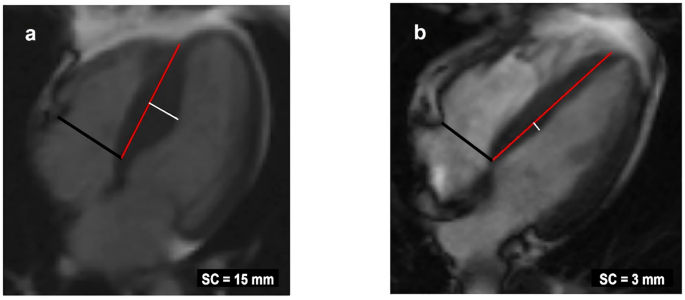

Image analysis was performed by experienced analysts (M.T., K.L., P.S., and M.H. with more than 10 years of experience in CMR) blinded to the clinical or genetic findings of the study subjects. SC into the LV was measured in end-diastolic 4-chamber images as the maximal distance between the LV septal endocardial border and a line connecting septal mid-wall points at the level of tricuspid valve insertion and at the level of apical right ventricular insertion on the LV, as described previously18. Figure 2 shows the SC measurements in a subject with HCM and in a subject with HHD. Previously, SC measurements have been used in only two reported studies, including our own group, and have demonstrated high reproducibility18,19. All other anatomical measurements of the CMR images were performed as described previously2,21. All the HCM patients had septal asymmetric hypertrophy and other types of HCM such as apical or concentric hypertrophy were not detected.

Measurement of septal convexity (SC) in end-diastolic 4-chamber cardiac magnetic resonance images (a) from a subject with hypertrophic cardiomyopathy and (b) from a subject with hypertensive heart disease. The black line is the tricuspid valve annulus. The red line is a reference line between the septal mid-wall at the level of the tricuspid valve and the insertion point of the right ventricle into the left ventricle at the apex. The white line represents the measured SC.